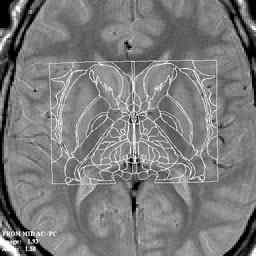

Magnetic resonance imaging (MRI) allows the acquisition of highly detailed structural information

about the soft tissues of the brain. Minute pathological alterations can be visualized, even before they can be

detected by other means. Stereotactical atlases based on this information are now used to achieve an exquisite

precision of location of the electrodes and probes and for planning the operation.